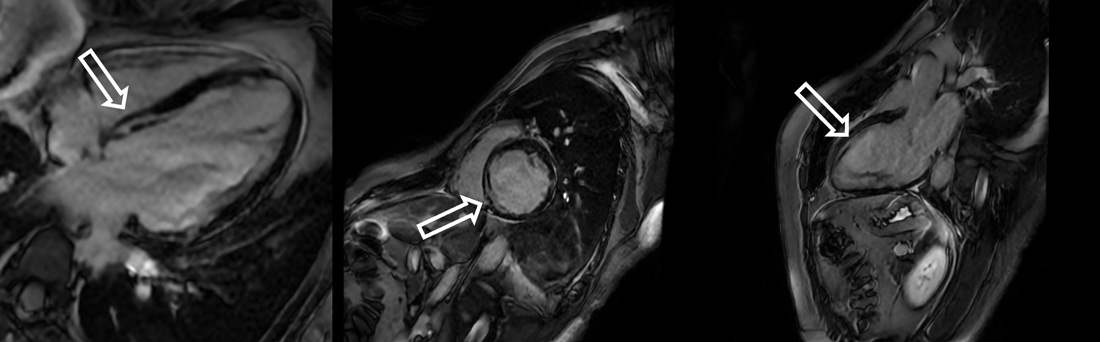

Non-Invasive Imaging

Cardiac MRI showed ischemic injury pattern with myocardial edema in the mid-basal infero-septal wall (T2 hyperintensity).

Subendocardial LGE involving infero-septal and anteroseptal segments (basal to apical).

Evidence of no-reflow in the mid-basal septum.

Cardiac MRI

- Cardiac MRI deemed essential to characterize myocardial viability, presence and distribution of ischemic scar before any revascularization.

- Cardiac MRI-based viability assessment remains pivotal to ensure appropriate selection of patients undergoing complex CTO intervention.